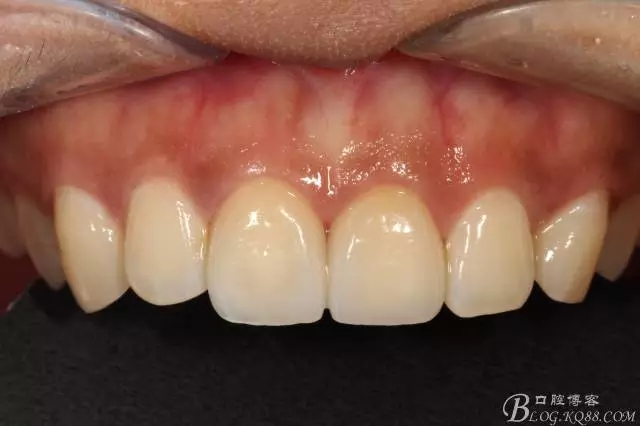

兩周后復(fù)查(訴11遇冷有點(diǎn)不適,因11備牙有點(diǎn)多,露牙本質(zhì)。囑注意不要進(jìn)食過冷過熱食物。癥狀約一個(gè)月后逐漸消失。)

兩周復(fù)查局部放大

復(fù)查舌側(cè)照

本來想拍個(gè)微笑像,可惜抓拍幾張都不自然,就留了這張。(兩周復(fù)查時(shí))